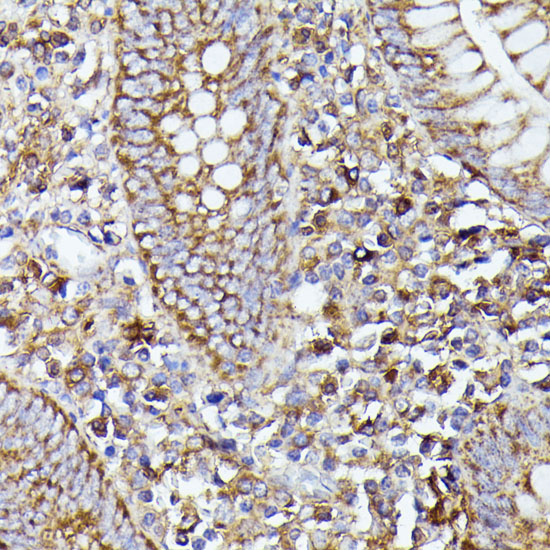

Immunohistochemistry of paraffin-embedded rat lung using NLRP3 antibody at dilution of 1:100 .

,

Immunohistochemistry of paraffin-embedded human appendix using NLRP3 antibody at dilution of 1:100 .

Immunohistochemistry of paraffin-embedded mouse spleen using NLRP3 antibody at dilution of 1:100 .